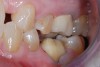

A 61-year-old female patient presented with a failed alloy restoration and missing the entire lingual surface of tooth No. 19 (Figure 2 and Figure 3). The argument could have been made to use either an onlay or a crown to replace the affected tooth. With the extent of the missing tooth structure, the malocclusion, and the patient's history of bruxism, treatment with a full-coverage restoration was selected to maximize longevity.

(2.) Preoperative images.

Figure 2

(3.) Preoperative images.

Figure 3